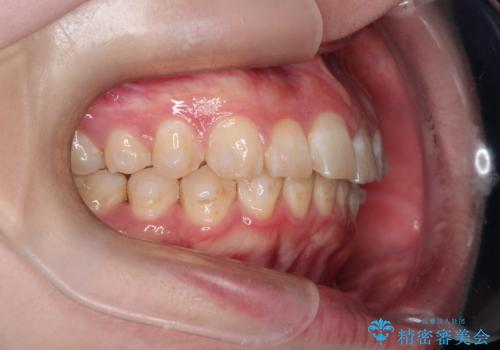

インビザラインで前歯のガタガタをきれいな歯並びへ

- 前歯のガタガタが気になるとのことで来院されました。

上顎の前歯の叢生があったのと、下あごの前歯が通常より1本欠損(先天欠損)していました。

上顎の歯と歯の間をわずかに削りスペースをつくり、並べる計画としました。インビザライン治療を選択されました。

しっかりとインビザラインを使用していただけたので、スムーズに治療を終了させることができました。